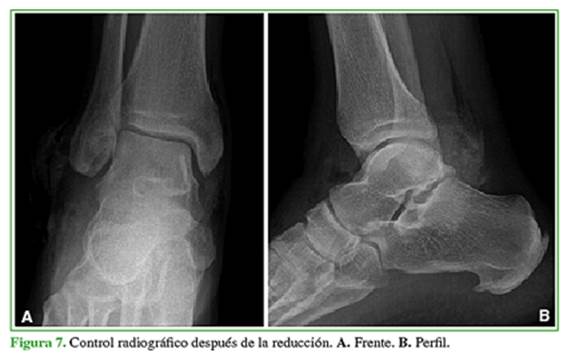

Hombre de 43 años que sufrió un traumatismo de tobillo derecho tras una caída desde un metro de altura. Consultó en la guardia de nuestro hospital el mismo día del traumatismo, tenía dolor, impotencia funcional y deformidad en dicho tobillo. Las radiografías mostraron una luxación periastragalina medial pura (Figura 6), por lo que fue sometido de urgencia a una reducción bajo anestesia (Figura 7).